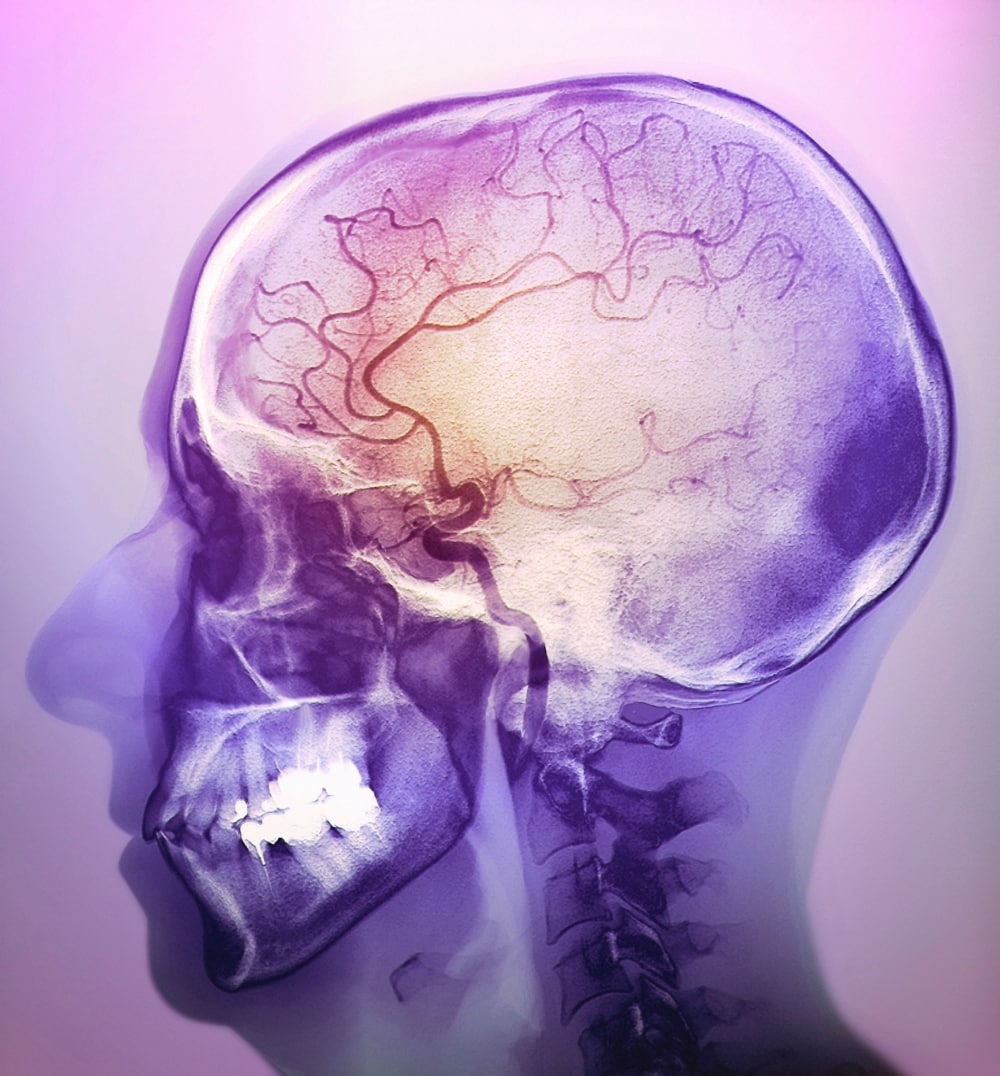

Bloedvoorziening van de hersenen

Er zijn 3 belangrijke arteriën die de hersenen van bloed voorzien. Vanuit de binnenste halsslagaders (arteria carotis interna) ontspringen 2 hersenslagaders (arteria cerebri anterior en arteria cerebri media), die de voorkant van de hersenen van bloed voorzien. De achterkant van de hersenen krijgen bloed vanuit de arteria basilaris. De hersenslagaders komen samen in de cirkel van Willis, een knooppunt van bloedvaten. Dit fungeert als reservesysteem dat de hersenen toch van bloed voorziet als een van de genoemde bloedvaten afgesloten raakt.

Een herseninfarct is veel lastiger te herkennen. Door een tekort aan zuurstof en voedingsstoffen kunnen natrium en calcium zich ophopen in de hersencellen. Hierdoor nemen de cellen extra water op en gaan ze zwellen. Na 3 tot 6 uur is bij 60% van de infarcten een hypo-intens signaal (een donkergrijze vlek) zichtbaar op de CT-scan. Met CT-angiografie of CT-perfusie kan een arts het infarct al eerder diagnosticeren. CT-angiografie maakt gebruik van contrast om de afzonderlijke bloedvaten in de hersenen in beeld te brengen. Ook CT-perfusie maakt gebruik van contrastvloeistof. In dit geval meet de arts hoe de doorstroming van verschillende hersengebieden is.